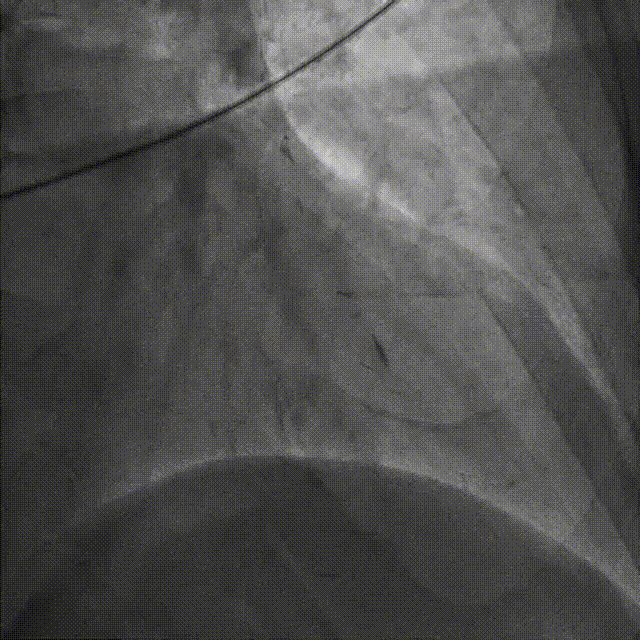

在HighTrack微导管的支撑下及逆向导丝的指引下,正向用Gaia First、Gaia Third、PILOT 200导丝反复尝试,均未能通过闭塞段进入血管真腔。

逆向重新送入一根SION Blue导丝反复尝试,最终进入正向指引导管内,推送逆向微导管至正向指引导管内,逆向送入RG3导丝至正向入口,正向沿RG3导丝推送微导管至LAD远段,撤出逆向导丝及微导管,交换一根SION Blue导丝至LAD远段。

依次用Pinoeer 2.0mm x 15mm、Pinoeer 2.5mm x 15mm球囊至病变处反复扩张,送入Marvel导丝至D1远段做保护,LAD行IVUS检查。

IVUS检查示:可见导丝全程走行与血管真腔,近中段重度纤维增生斑块伴局部钙化,远段血管床废用性萎缩。